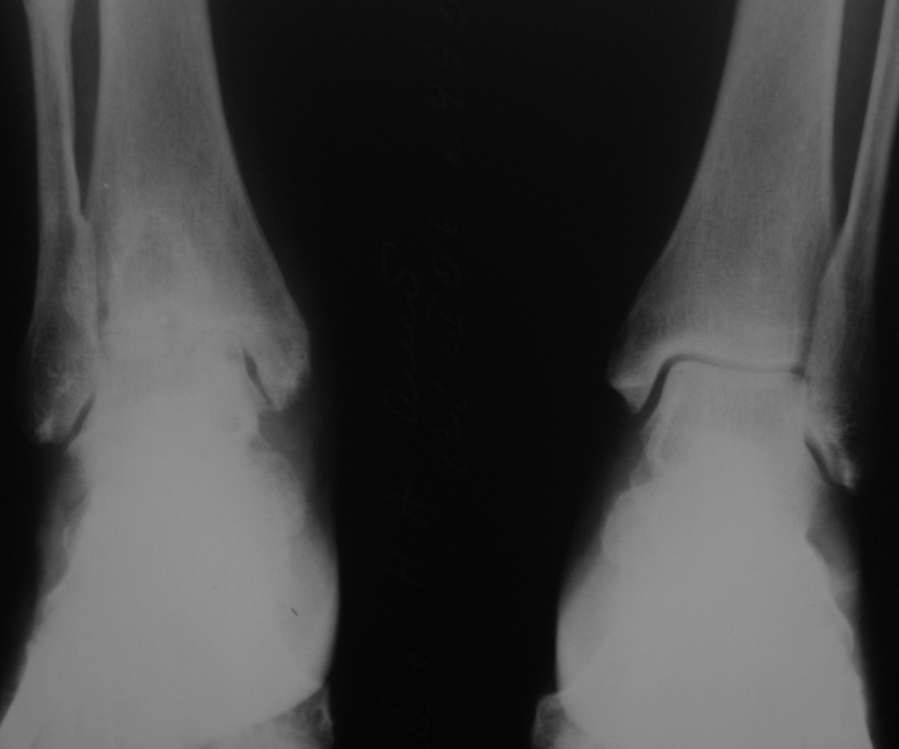

Уважаемые коллеги, разъясните ситуацию.Пациентка, 45лет. 9 месяцев назад произведен синтездвухлодыжечного перелома правой голени.

Конструкции на данный момент удалены. Объем движений на фото. Сейчас беспокоят скованость в области сустава, боли к концу рабочего дня - классическая клиника артроза.Пропила 4 курса найз. Откуда артроз такой выраженности (на рентгенограмме)? Поможет ли консервативное лечение и какое поможет наверняка?

Артроз, во-первых, вследствие неконгруентности суставных поверхностей - имеется укорочение малоберцовой кости; во-вторых имеется синостозирование берцовых костей (вместо тугоэластисчного синдесмоза).

>Артроз, во-первых, вследствие неконгруентности суставных поверхностей - имеется укорочение малоберцовой

Но укорочение - 3мм, и потом суставная поверхность наружной лодыжки не несет осевой нагрузки

>во-вторых имеется синостозирование берцовых костей (вместо тугоэластисчного синдесмоза).

Даже если это были оригинальные имлантаты "Synthes", то к "АО" этот остеосинтез не имеет ни какого отношения. Потому, что вся философия АО в отношении переломов лодыжек основана на том, что наружная лодыжка это нагружаемая часть сустава, на которую приходится примерно 1\6 веса тела. Восстановление длины м\б кости является приоритетным, и наружную лодыжку называют ключом г\ст сустава.

"Стягивающий винт на синдесмоз" противоречит АО, т.к. этот винт должен быть позиционным и не должен создавать компрессиию на уровне сочленения берцовых костей и между наружной лодыжкой и таранной костью. Стягивающий винт - основная причина синостоза на месте синдесмоза.

этих-то 3 мм и достаточно для формирования артроза. Наружная лодыжка - ключ к голеностопному суставу!